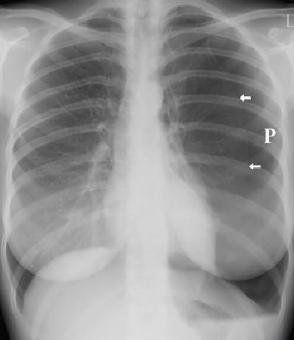

与其他致命性胸痛不同的是,气胸的诊断要简单得多。疑似气胸患者,进行常规胸片或胸部CT检查,在影像学上见到肺野中纹理消失和被压缩的肺与气体之间形成的气胸线,就可确诊气胸(见图8)。

图8 气胸的胸部X线表现(白色箭头所指为气胸线)